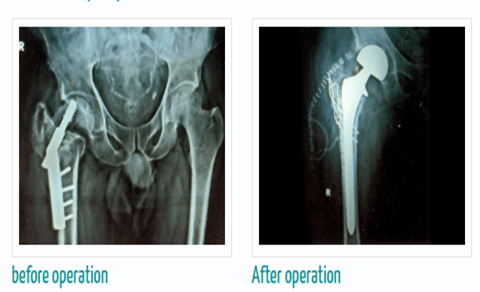

Complex Knee & Hip Replacement Surgeries

Our surgeons are highly experienced in handling complex cases like bow legs (varus), knock knees (valgus), or wind-swept legs, and have considerable expertise in revision joint replacement surgeries.